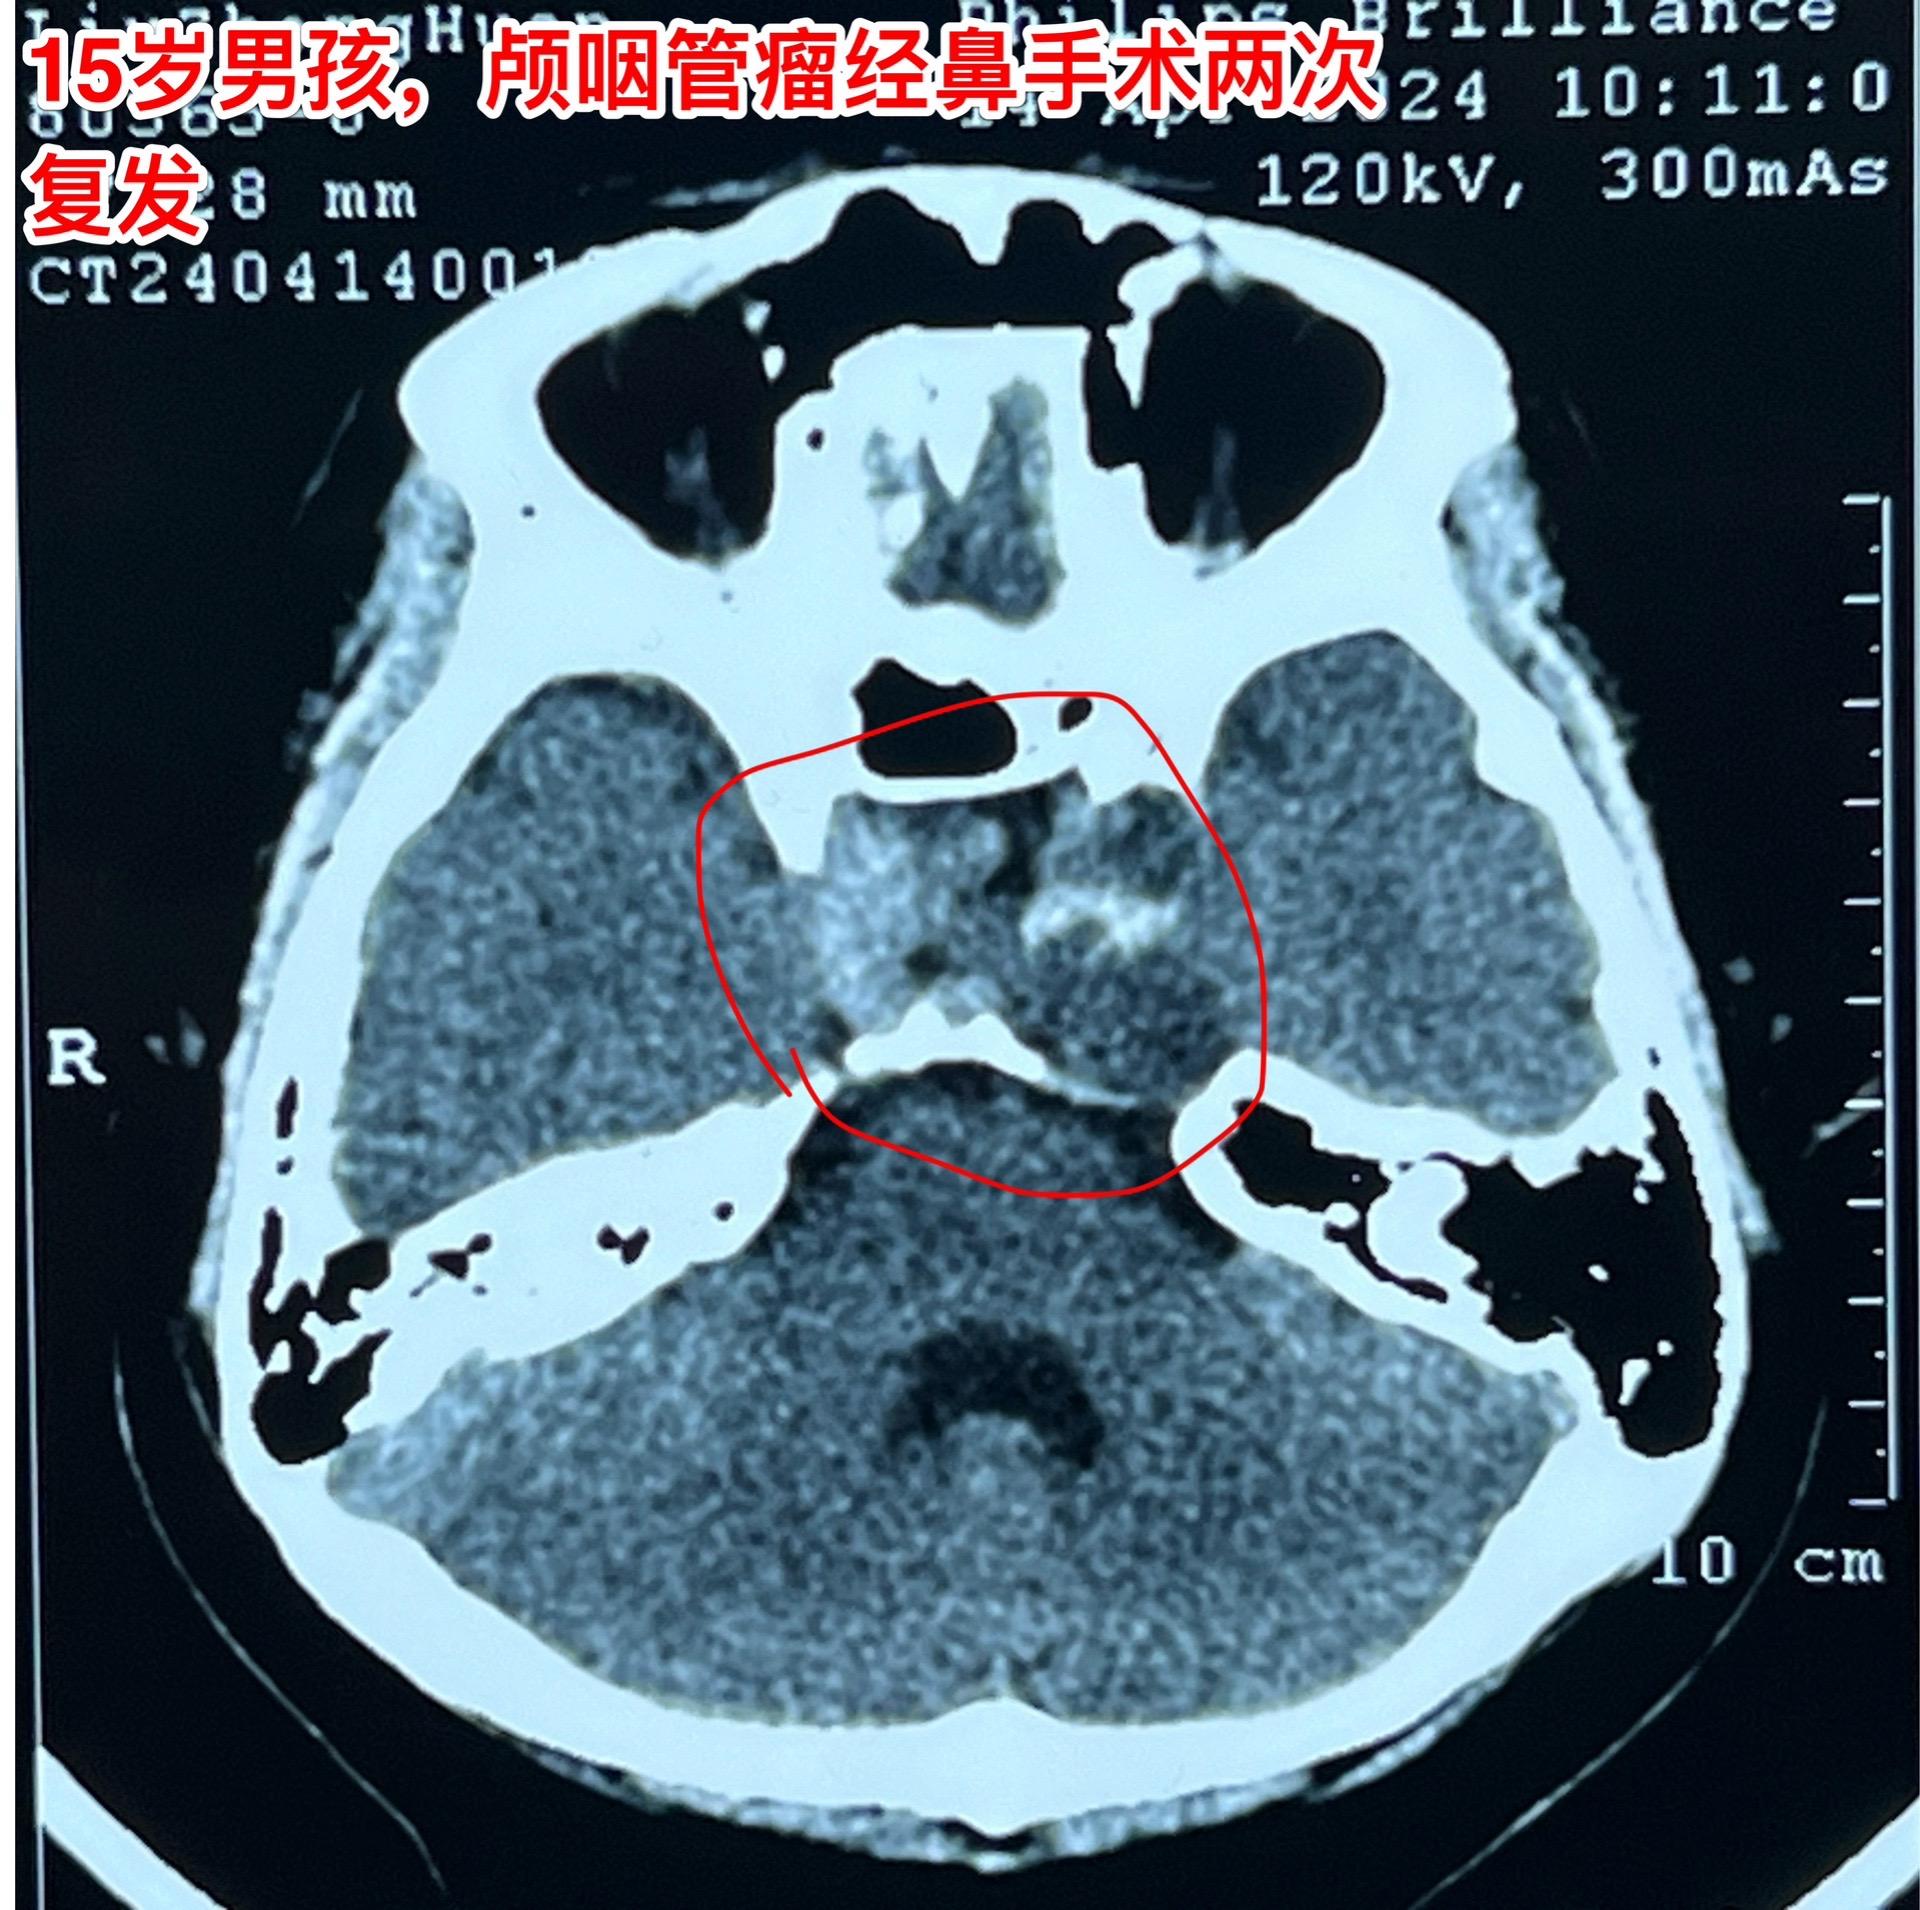

良性肿瘤也不一定容易治愈,颅咽管瘤就是。这个15岁大连市的男孩子因为颅咽管瘤先后作了两次手术,两次手术都是经鼻内镜手术。现在又复发了!从图片可以看见,这次肿瘤侵入左右两侧海绵窦,更难切除了。

在我科作了第三次手术,这次采用开颅手术。这样的手术医生很担忧出现脑脊液鼻漏的。这个病人手术后没有出现脑脊液鼻漏。

颅咽管瘤之所以容易复发是因为没有被彻底切除,如果彻底切除了也是可以治愈的。